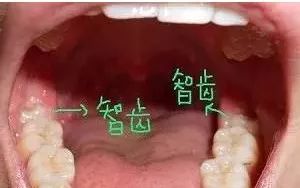

智齿,是口腔最靠近喉咙的牙齿,一般是人于16岁或之后才生长出来。一般来说,大多数人从门牙牙缝开始,由一侧门牙向后数,如果有第八颗牙,它就是智齿。

智齿在X线片上很清晰↓↓

*理论上人应该会有四颗智齿,但是一般不会全部长出来,很多人只会长出一颗或两颗,也有可能智齿是完全埋伏的,隐患和拔除难度都比较大。